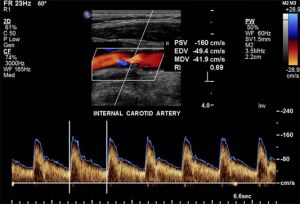

Carotid Duplex Ultrasound

Carotid duplex ultrasonography is the most commonly used non-invasive test for carotid occlusive disease. It combines B-mode ultrasound and Doppler ultrasound, providing both anatomical imaging of the vessel and information on flow velocity. The parameters used to classify the severity of stenosis include peak systolic velocity (PSV), end-diastolic velocity, and the ICA/CCA PSV ratio. Compared to conventional intra-arterial digital subtraction angiography (DSA), duplex ultrasound has good ability to detect high-grade symptomatic carotid artery stenosis (89% sensitivity, 84% specificity) and is excellent for detecting occlusion (96% sensitivity, 100% specificity) (Figure 7).

Peak Systolic Velocity (cm/sec) and ICA Stenosis (% diameter)

- PSV 125 – 225 cm/sec → 50–70% ICA stenosis

- PSV 225–350 cm/sec → 70–90% ICA stenosis

- PSV >350 cm/sec → 90% ICA stenosis